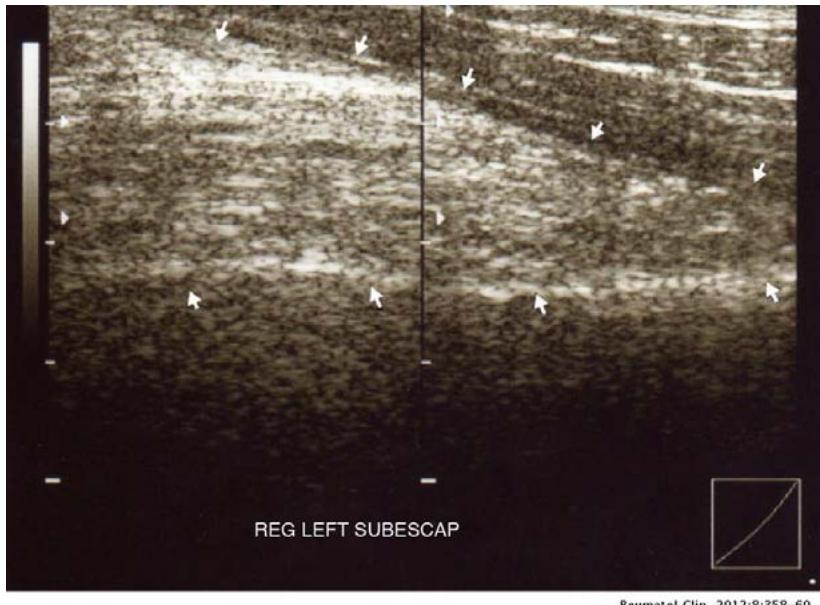

Various imaging modalities such as ultrasound, CT, and MRI play an important role in establishing diagnosis. Ultrasound examination of elastofibroma shows an alternation of linear sections that have a different echo signal and form a layered structure \[23\](Fig. 2).

Figure 2: Ultrasound image showing a solid mass with alternating hypo- and hyperechoic areas below the serratus anterior (arrows).